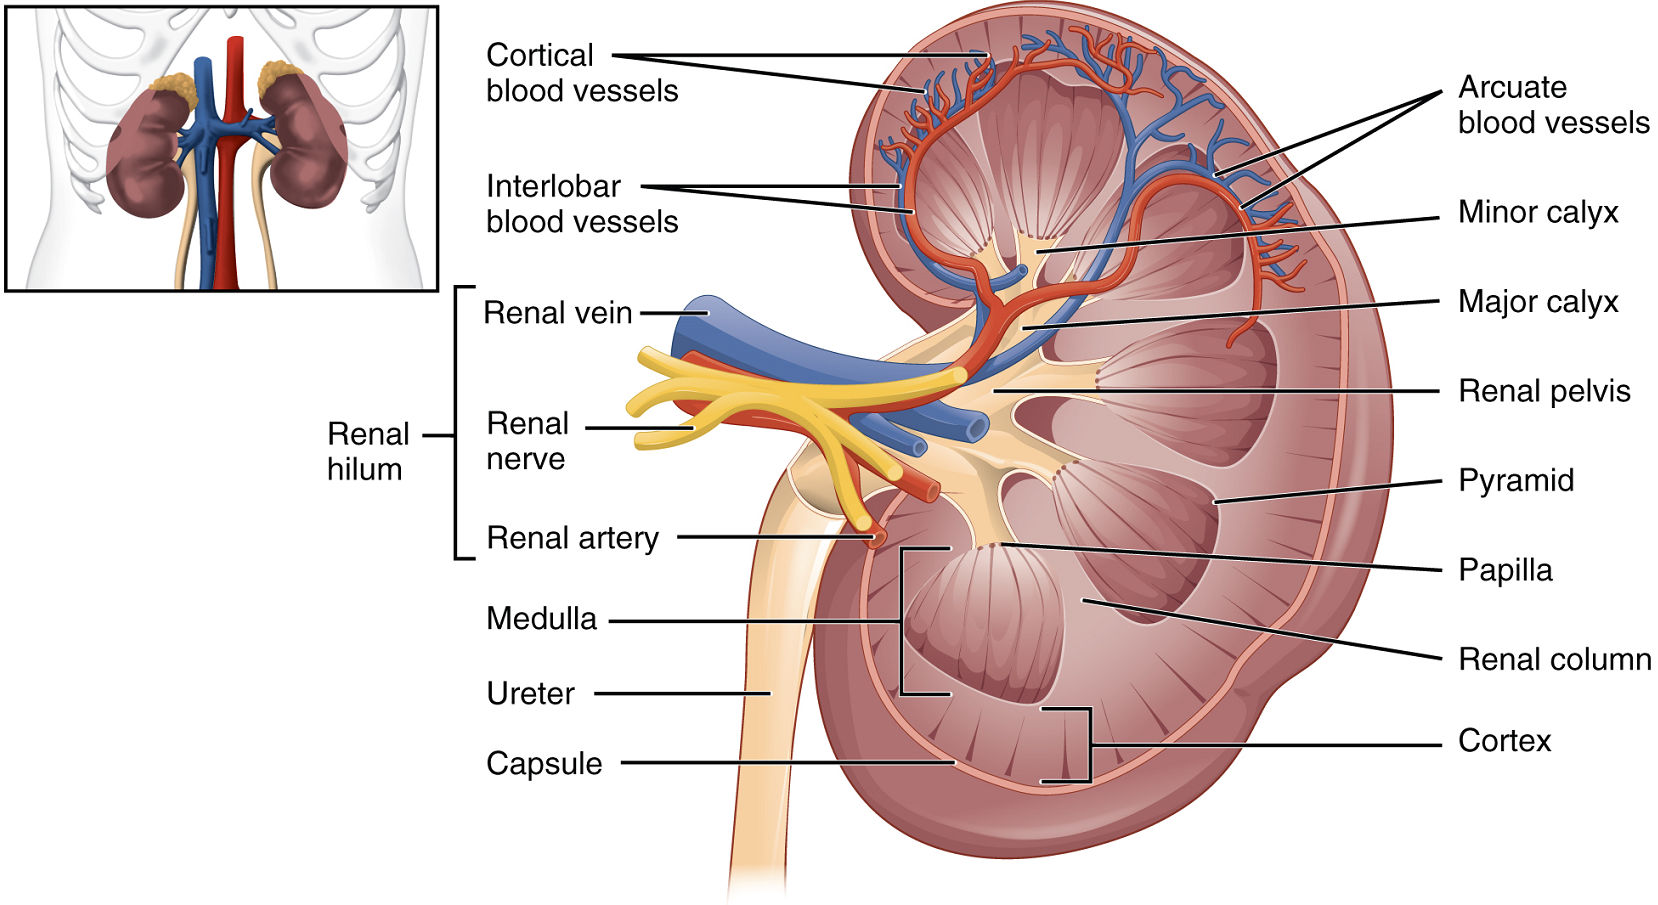

Internal Anatomy: A frontal section through the kidney reveals an outer region called the renal cortex and an inner region called the medulla (Figure 2). The renal columns are connective tissue extensions that radiate downward from the cortex through the medulla to separate the most characteristic features of the medulla, the renal pyramids and renal papillae. The papillae are bundles of collecting ducts that transport urine made by nephrons to the calyces of the kidney for excretion. The renal columns also serve to divide the kidney into 6–8 lobes and provide a supportive framework for vessels that enter and exit the cortex. The pyramids and renal columns taken together constitute the kidney lobes.

Renal Hilum: The renal hilum is the entry and exit site for structures serving the kidneys: blood vessels, nerves, lymphatics, and ureters. Emerging from the hilum is the renal pelvis, which is formed from the major and minor calyces in the kidney. The smooth muscle in the renal pelvis funnels urine via peristalsis into the ureter. The renal arteries form directly from the descending aorta, whereas the renal veins return cleansed blood directly to the inferior vena cava. The artery, vein, and renal pelvis are arranged in an anterior-to-posterior order.